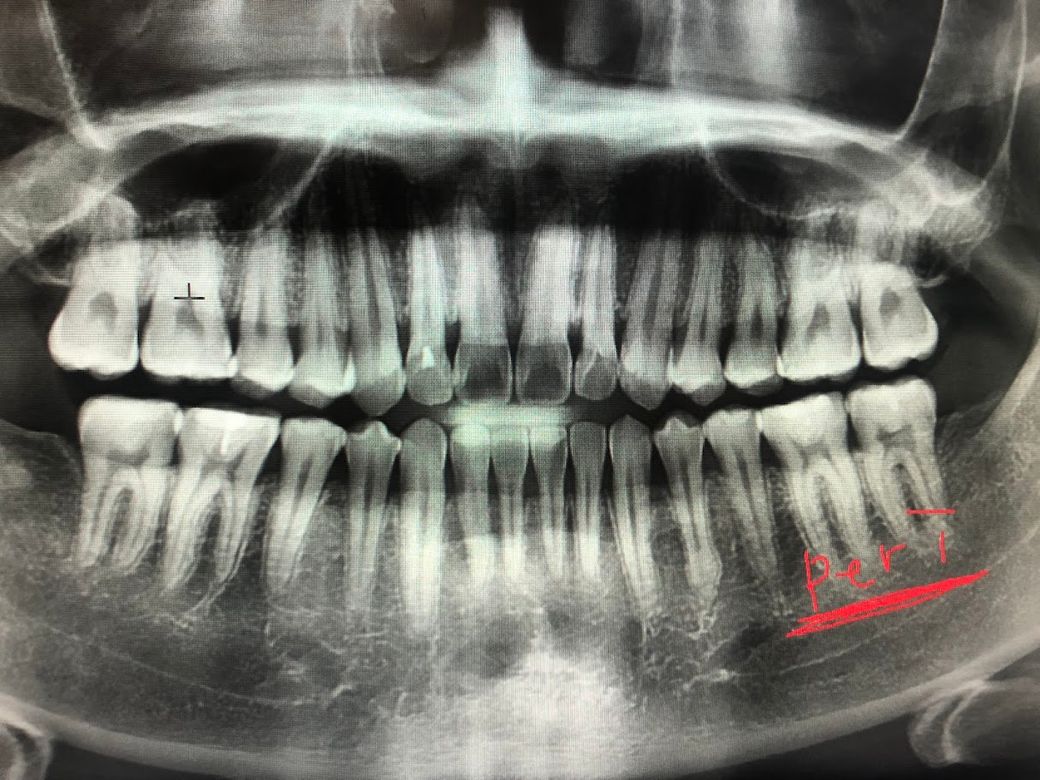

제 치아 엑스레이 상태가 궁금합니다.

현재 26살 입니다

치간칫솔을 사용중인데 또래 20대에 비해서 잇몸이 너무 내려간거 같아요

치아들에 ss, m 사이즈가 그냥 쑥쑥 들어가요

그리고 치아들 상태도 확인하고 싶어요

• 2번 째 사진

x-ray 사진에서 잇몸뼈(치조골) 상태는 정상인 것으로 보입니다. 치간 치솔이 들어가는 것은 본인 치간치솔을 잘 사용해서 일 수도 있습니다. 잇몸 상태는 구강검사 하여 육안으로 보아야 합니다.

2. 잇몸뼈가 아주 많이 퇴축되진 않았습니다

3. 어금니 부위 마모가 어느정도 진행되었습니다이갈이나 이악물기 습관이 있다면 고치시기 바랍니다